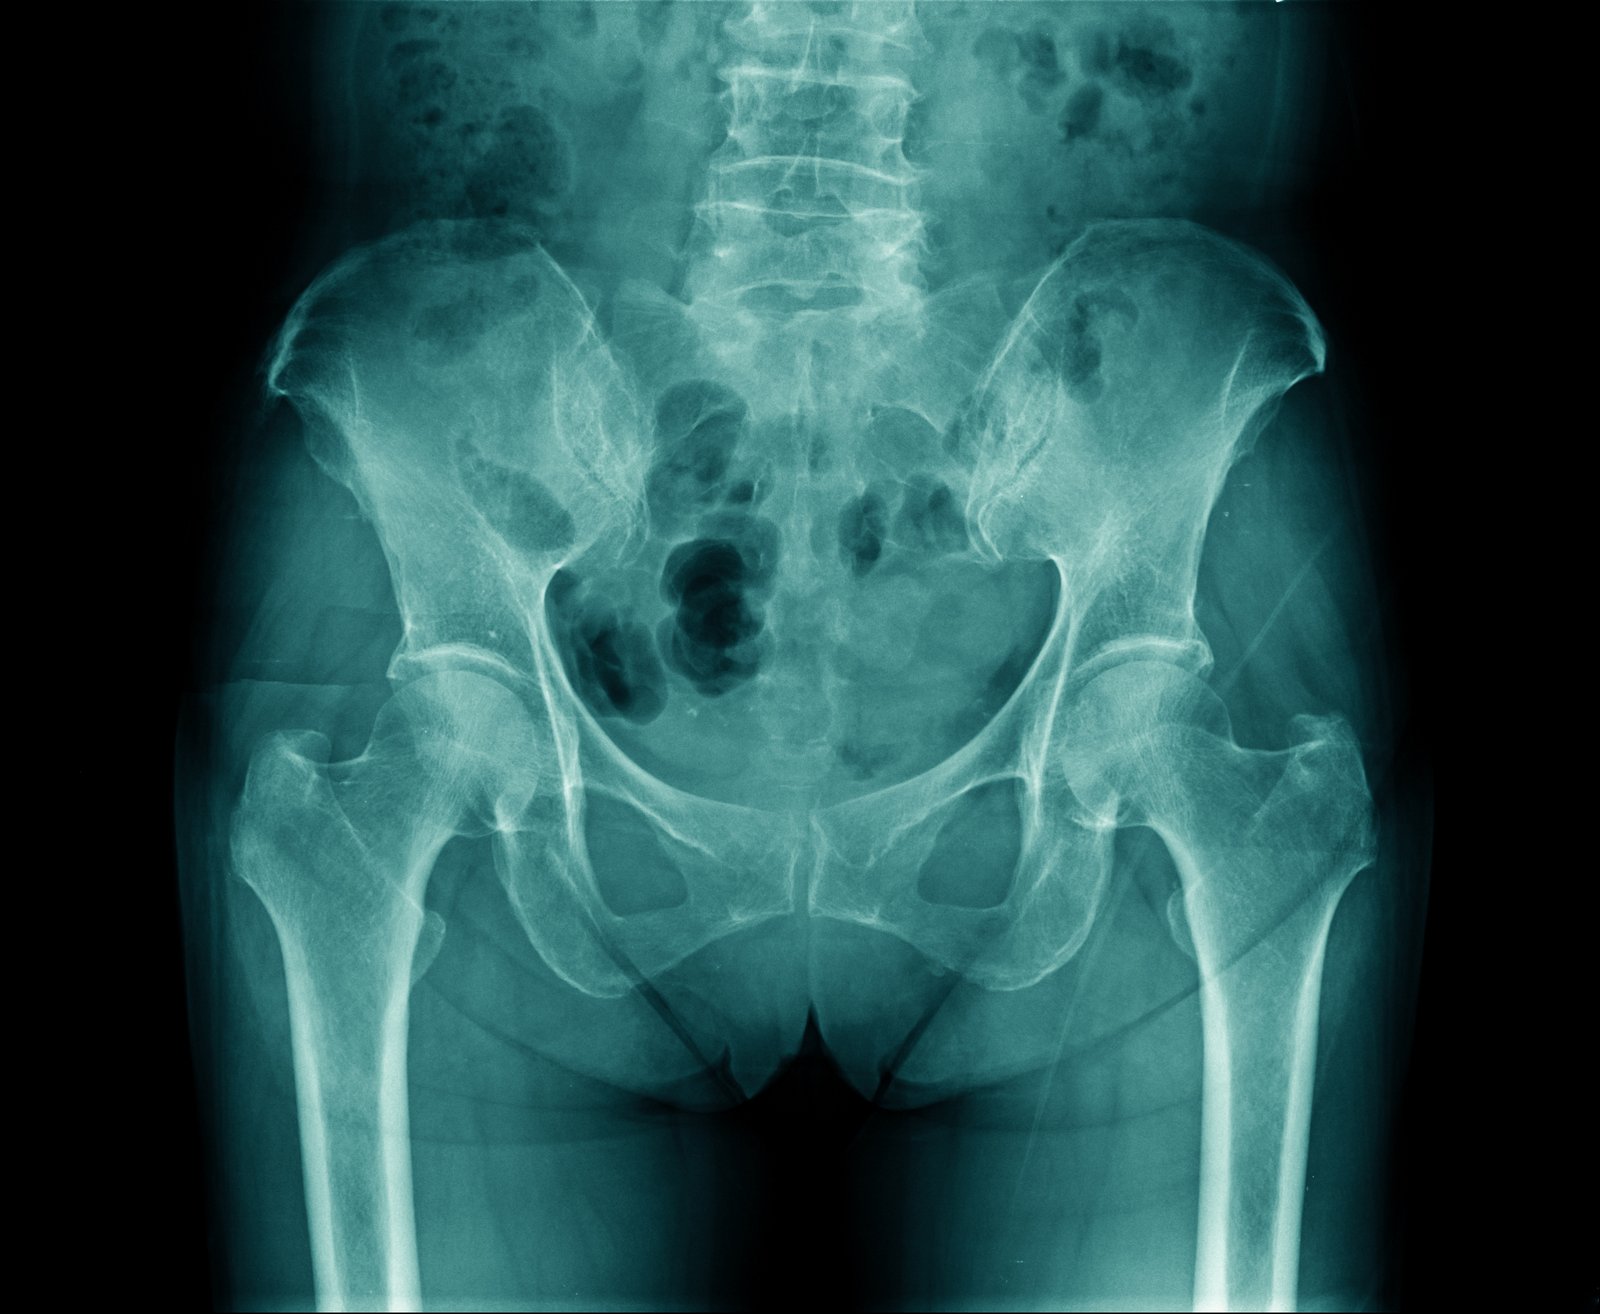

Notre équipe propose une imagerie numérique de haute définition pour le bassin, la hanche et les articulations sacro-iliaques. Les clichés comprennent des incidences face, profil, 3/4 et des prises dynamiques adaptées à votre clinique.

Nous visons un diagnostic précis dès le premier passage. Grâce à un plateau technique fiable, nos radiologues mesurent les axes et interlignes pour fournir des comptes rendus exploitables par votre médecin ou chirurgien.

La radiologie met en évidence fractures, signes d’usure (pincement, ostéophytes) et conflits fémoro-acétabulaire.

- Nous précisons les clichés standards : bassin de face, incidences ciblées et hanches en 3/4.

Le technicien installe et positionne en face puis en profil selon l’indication. Nous réalisons des incidences ciblées des articulations sacro-iliaques pour une imagerie précise.

La radiologie numérique couvre les examens standards : bassin, hanche, sacro‑iliaques, rachis en téléradiographie, thorax et abdomen sans préparation.

Qualité d’image et mesures pour un diagnostic fiable

Nos outils améliorent la finesse des détails osseux et la reproductibilité des mesures. Cela aide au suivi post‑opératoire et à la décision thérapeutique.

| Radiologie numérique | Contours articulaires nets, mesures fiables | Sur site |